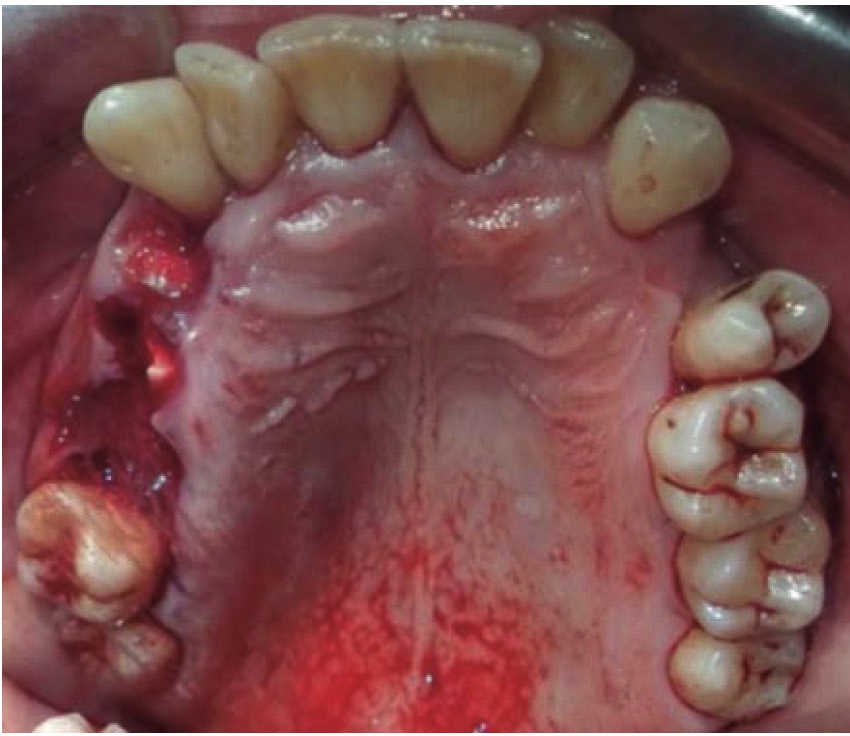

The first case was that of a 30 year old male, with diagnosis of fracture of left mandibular body caused by firearm. The patient was assaulted after a fight which took place when he was leaving a nightclub, he received a bullet shot at a 4 meter distance. Patient exploration revealed edema at cervical, middle third and lower facial levels; he exhibited entry orifice at the left genial region and exit wound at the right submandibular level (Figure 4). Intraoral examination revealed a wound in the mandibular alveolar process at the fracture line, and absence of teeth (Figure 5). Treatment was initiated under general anesthesia with airway stabilization provided by tracheotomy. Debridement of wound edges was performed locally, with surgical soap washes, physiological solution and wound suture. After soft tissue treatment was completed, initial occlusal stability was attempted with an Erich-type bar arch. The patient was hospitalized under a therapeutic scheme of immunization, antibiotics and analgesics.

A 48 year old male arrived for treatment with diagnosis of facial wound caused by firearm. He was assaulted by a third party in the street. He did not inform of the shooting distance. The patient exhibited a projectile entry wound at the right genial region and no exit wound (Figure 8). Intra oral examination revealed a wound in the right cheek, tooth fracture at the level of the upper right hemi-arch, with fractures at the dental neck of first and second premolars and first molar (Figures 9 and 10) involvement. Under local anesthesia, the wound was washed with surgical soap and abundant physiological solution. The tongue was superficially dissected, the bullet was extracted (Figure 11), hemostasis was performed and wounds were sutured. Tooth remains were considered rests and deemed unable to be restored, for that reason they were extracted. The patient attended periodic evaluations with suitable healing of soft tissues and alveolar process. The patient refused implant therapy due to financial considerations, he was thus referred to be rehabilitated with a removable prosthesis.

A 73 year old female with diagnosis of fracture of left mandibular body due to firearm projectile (Figure 12). The patient informed she was assaulted in the street, and upon offering resistance to the theft of her vehicle, she was shot at a distance of two meters. She arrived at our institution eigt days after the assault, having previously been treated in another hospital. Physical exploration revealed hyperemic area and volume increase in fluctuating left submandibular region; entry orifice at left submandibular level with presence of fetid whitish secretion and closed exit wound at right cervical level. Intraoral examination revealed partial edentulism, with multiple maxillary septic foci, and at the left mandibular fornix, a root remnant of the first molar in the fracture line as well as accentuated mobility of the mandibular segment caused by fracture which hindered deglutition.